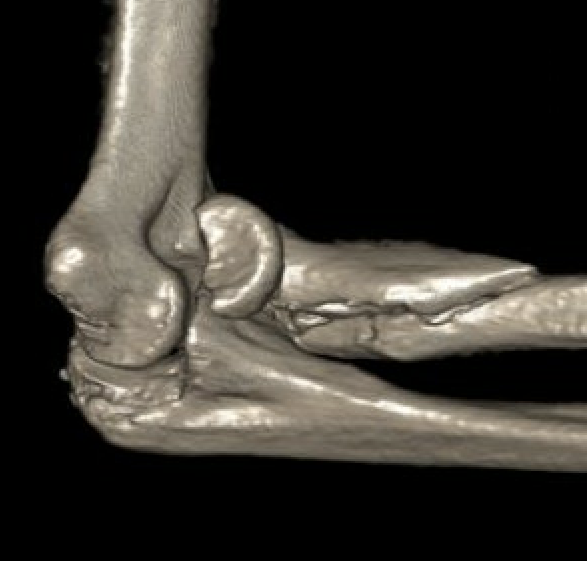

Completely displaced radial neck fracture

ORIF with plates